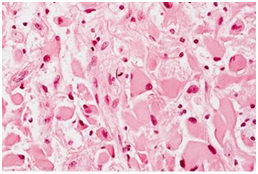

根据肿瘤的组织学特点,星形细胞瘤可分为纤维型、原浆型、肥胖细胞型等类型。下面是在显微镜下的常见的星形细胞瘤分型。

肥胖性星形细胞瘤 间变性星形细胞瘤